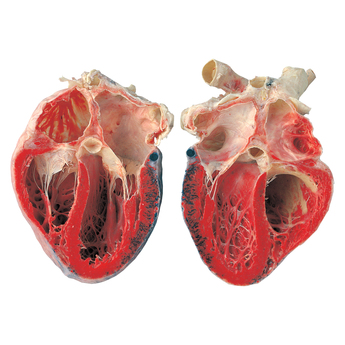

The process of plastinations follows the idea that if you inject a body with plastic to coat the cells then it will be preserved in its original state - this follows the same idea as coating the outside in a thick layer of plastic but allows the detail of the organ to be seen for what it is and in closer detail. I find these works hugely interesting and enlightening and has really allowed me to see the shape and textures of the muscle and nerve tissues. I dislike the fact that the pieces are stationary because as biological organisms we are continually moving and changing whereas here they have only captured one point in time, therefore a lot of work is needed in order to understand a biological sequence such as an electric impulse. This makes a lot of Dr. Hagens work redundant for my own use. Even though this may be the case the works ( like the plastinated brain) have provided a solid understanding of if shape and use - this is something that is essential to my work and without wich I could not proceed. I hope to meet similar standards of work in my project - including things like biological accuracy and aesthetic and natural symmetry (not quite exact). Looking at these bodies has pushed me to work with real organs and to study them fully.

The organs such as the brain and heart are more accurately portrayed when preserved with the method of plastination. This is because it retains the detail of each tissue while also keeping its three dimensional shape. This has shown its importance as when resin is used for the same purpose the original organ can not be touched. Plasination allows the original organ to show in its full glory meaning that it can actually be touched and held a very important part of learning and understanding.

While at the exhibition I wrote some notes and did some sketches in the form of a flow chart to help me understand the way in which the nervous system and the thought process works together. I wanted to understand further how a thought is a physical thing. In the process I began to realise that we are entirely run off electricity. I made the link that the process of a thought -> impulse -> action is a whole string of electrical circuits. By taking the information given to me in this exhibition and producing it in a concise note from made it clear and easy to see. It is a link that I feel particularly good about as it means that the vision for my project can open up and show not just the brain but other aspects of the body as well. Although this theory brings my idea in a very satisfying circle linking back to the beginning of the thought process, I dislike the fact that although true I feel like it is a very tenuous link to make and that I am stretching biological fact to fulfil my aim which is not what I was trying to achieve in this project. I am trying to meet accurate biological standards so to do this I must use true, not interpreted, information. This has caused the development of my idea by using this idea of multiple circuits but only with the heart muscle ( which uses electrical impulses to stimulate a heart beat) in comparison to stryated muscle which only receives electrical impulses as a signal. This means that I can use the information from this exhibition accurately while also adding my own thoughts to the process.